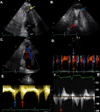

Case report: We present a case of HCM with midventricular hypertrophy and obstruction diagnosed after a CT scan of the abdomen incidentally revealed a filling defect in the left ventricular apex. Transthoracic echocardiography demonstrated mid left ventricular hypertrophy and obstruction, as well as an aneurysmal apex containing a large thrombus. Cardiovascular MRI showed a spade-shaped left ventricle with midcavitary obliteration, an infarcted apex and regions of myocardial fibrosis. Due to the risk of embolization and a relative contraindication to anticoagulation, the patient underwent surgery including thrombectomy, septal myectomy and aneurysmal ligation.